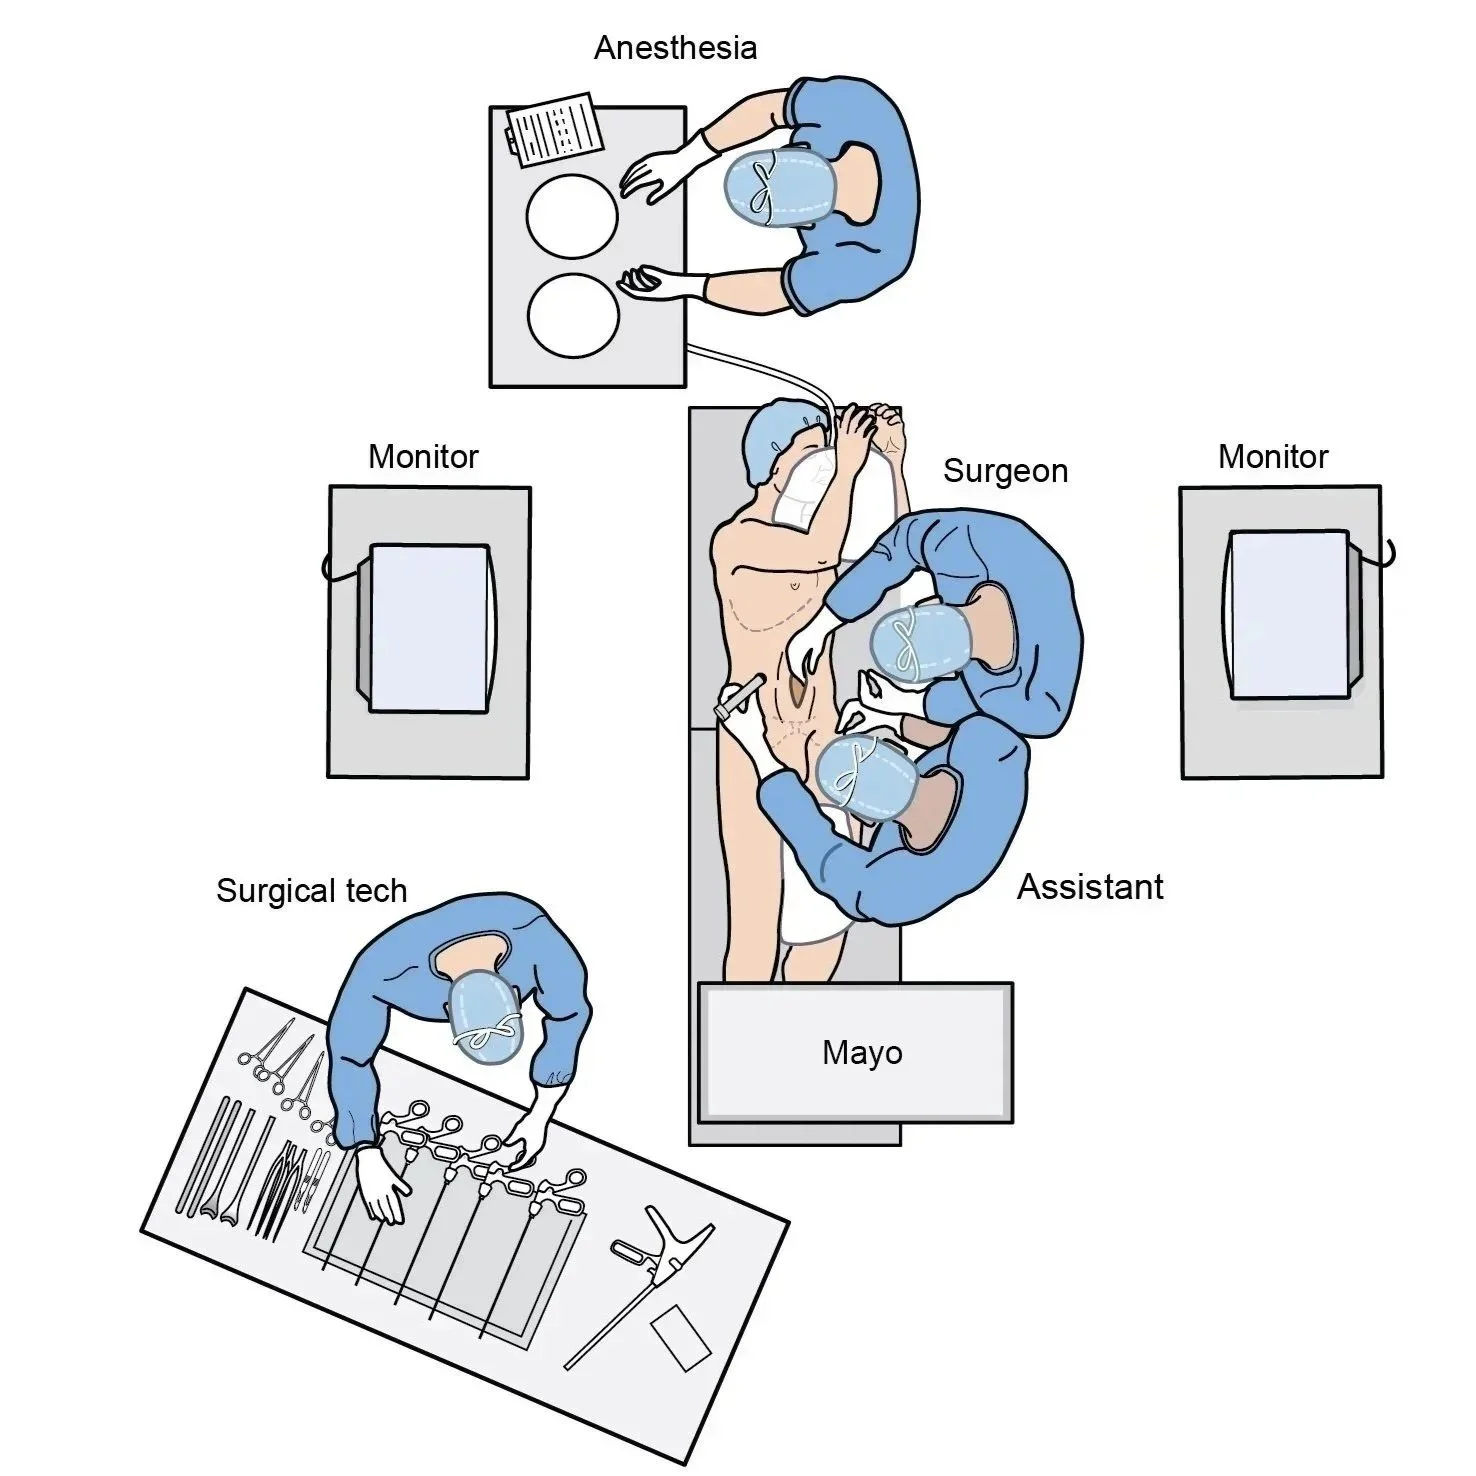

Instructional illustrations are used to teach or explain medical information to a specific target audience. Examples include;

Medical device marketing

Training guides for health-care providers.

Surgical illustrations visually depict operative techniques, surgical anatomy, and complex procedures. They are created with high anatomical accuracy and serve as a visual bridge between complex surgical knowledge and learners, clinicians, or patients.

Medical Device Marketing